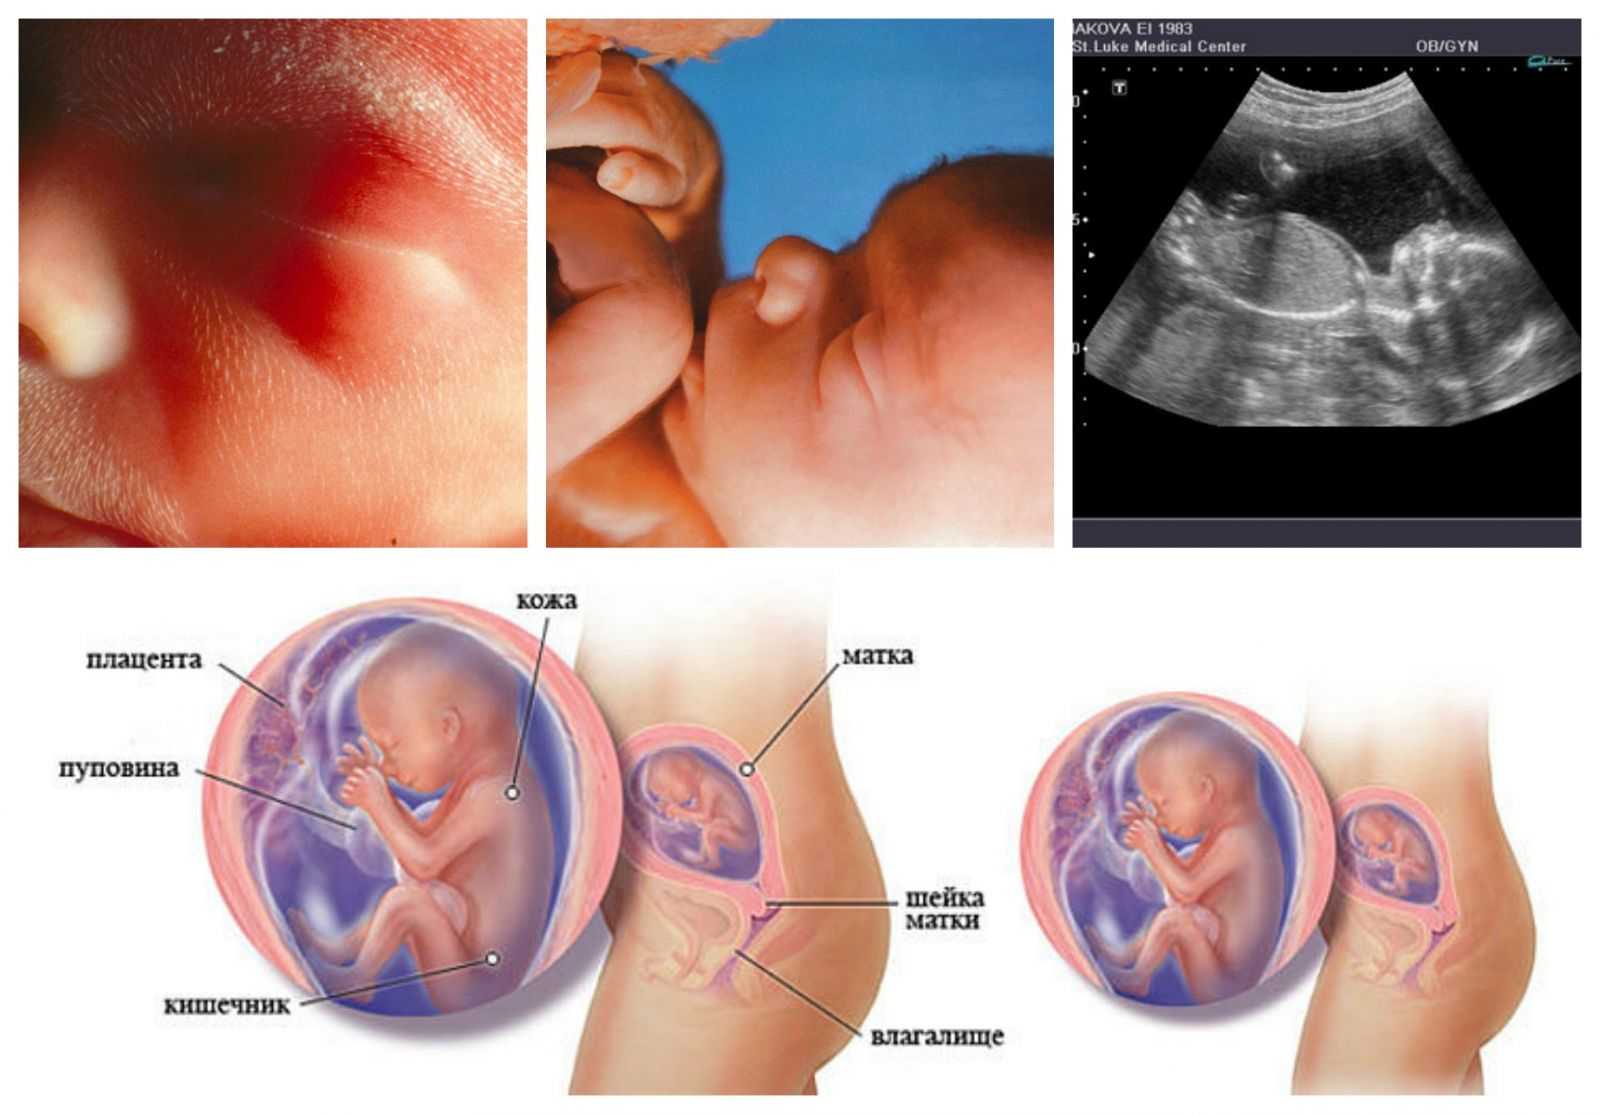

Твой живот растет, и на 22 неделе ты можешь заметить на коже красные полоски – растяжки. Появляются они на животе, бедрах, груди и ягодицах. Впрочем, вполне вероятно, что ты избежишь растяжек – практически половина беременных не сталкиваются этими неприятными отметинами. Цвет растяжек может быть разным – от розового до коричневого, с течением времени они становятся все более яркими. Начни пользоваться кремом от растяжек, как только заметишь их появление, это поможет справиться с проблемой.

На твоем лице, руках, верхней части груди и шее могут сейчас появиться сосудистые звездочки. Вызваны они высоким уровнем эстрогена при беременности и, как правило, исчезают после родов.

УЗИ скрининг во втором триместре беременности.

Второй триместр охватывает 18,19,20, 21 или 22 неделю беременности, оптимальный срок — 19-20 недель. Так же, как и в первом триместре, пройти УЗИ в этот период должны все будущие мамы.

Как выглядит плод на УЗИ второго триместра?

На 19-22 неделе беременности ребенок весит уже 400—500 грамм, а его рост увеличивается до 22-27 см. Теперь врач может рассмотреть малыша на УЗИ во всех подробностях и показать будущим родителям, лицо, пол ребенка, сколько у него пальцев.

Как выглядит малыш

К концу пятого акушерского месяца своего развития вес малыша уже составляет 300 г, а рост достигает 27 см. При УЗИ можно определить остальные размеры тела, по которым врач судит о темпе развития ребенка. Диаметр головки, грудной клетки и живота одинаковые и составляют 43 мм, длина бедра – 31 мм. Плацента продолжает увеличиваться, толщина ее равняется 21-22 мм.